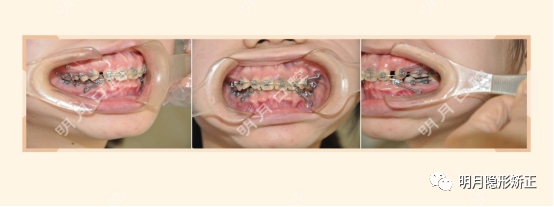

在看到她口內的矯治器那一瞬間,我居然承認我自己有點孤陋寡聞了,因為她的口內矯治器,我居然看不出是什麼類型。

原來打了四顆支抗釘,一根軟綿綿的弓絲,用了五根拉簧在拚命的拉着虎牙。

(圖為初診口內照)